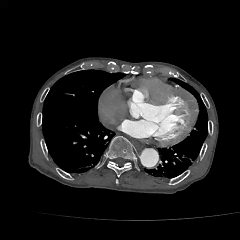

现病史:患者8小时前无明显诱因下出现头晕伴恶心呕吐,呕吐物为胃内容物,无视物旋转,无呕血黑便,无胸闷气促,无胸痛,遂至当地医院就诊查。CTA提示主动脉瘤,腹主动脉多发钙化,胸主动脉多发钙化斑块。

▶ 术前影像学资料

IV型胸腹主动脉瘤,瘤颈和双侧髂动脉严重扭曲,瘤体巨大,内脏分支血管开口角度倾斜